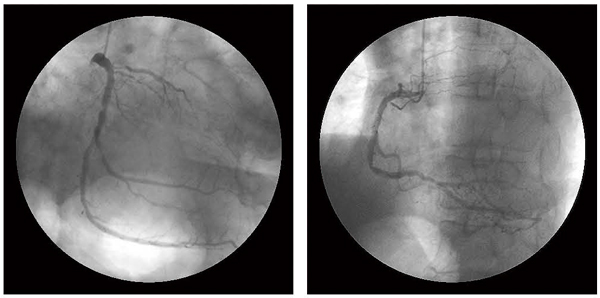

図7 CAG

LAD#6に完全閉塞,LCX#14に高度狭窄, RCA#3に中等度狭窄病変を認める。

これらの結果から,ザイオソフト社製ワークステーション「ZIOSTATION」の「CT/SPECT心臓フュージョン」ソフトウェアを用いて,CT-SPECT Fusionの画像構築を行ったところ,RCA#3の残存狭窄病変に一致する虚血とLAD#6のCTO病変に一致する梗塞+虚血性変化が認められた(図5,6)。CT-SPECT Fusionの結果から,残存病変に対する血行再建の必要性が考慮され,回復期にCAGを行った(図7)。再検したCAGにおいて,LADのCTO病変に関してはPCI困難と判断された。RCAのステント留置部位に関しては亜急性期の再狭窄は認めなかったが,末梢側に有意狭窄を認め,LCX

#14の高度狭窄病変と合わせ,いずれもCTCAと同様の所見であった。以上から,冠動脈バイパス手術(CABG)による血行再建が最適と判断され,第27病日に冠動脈3枝に対しCABGを施行した。